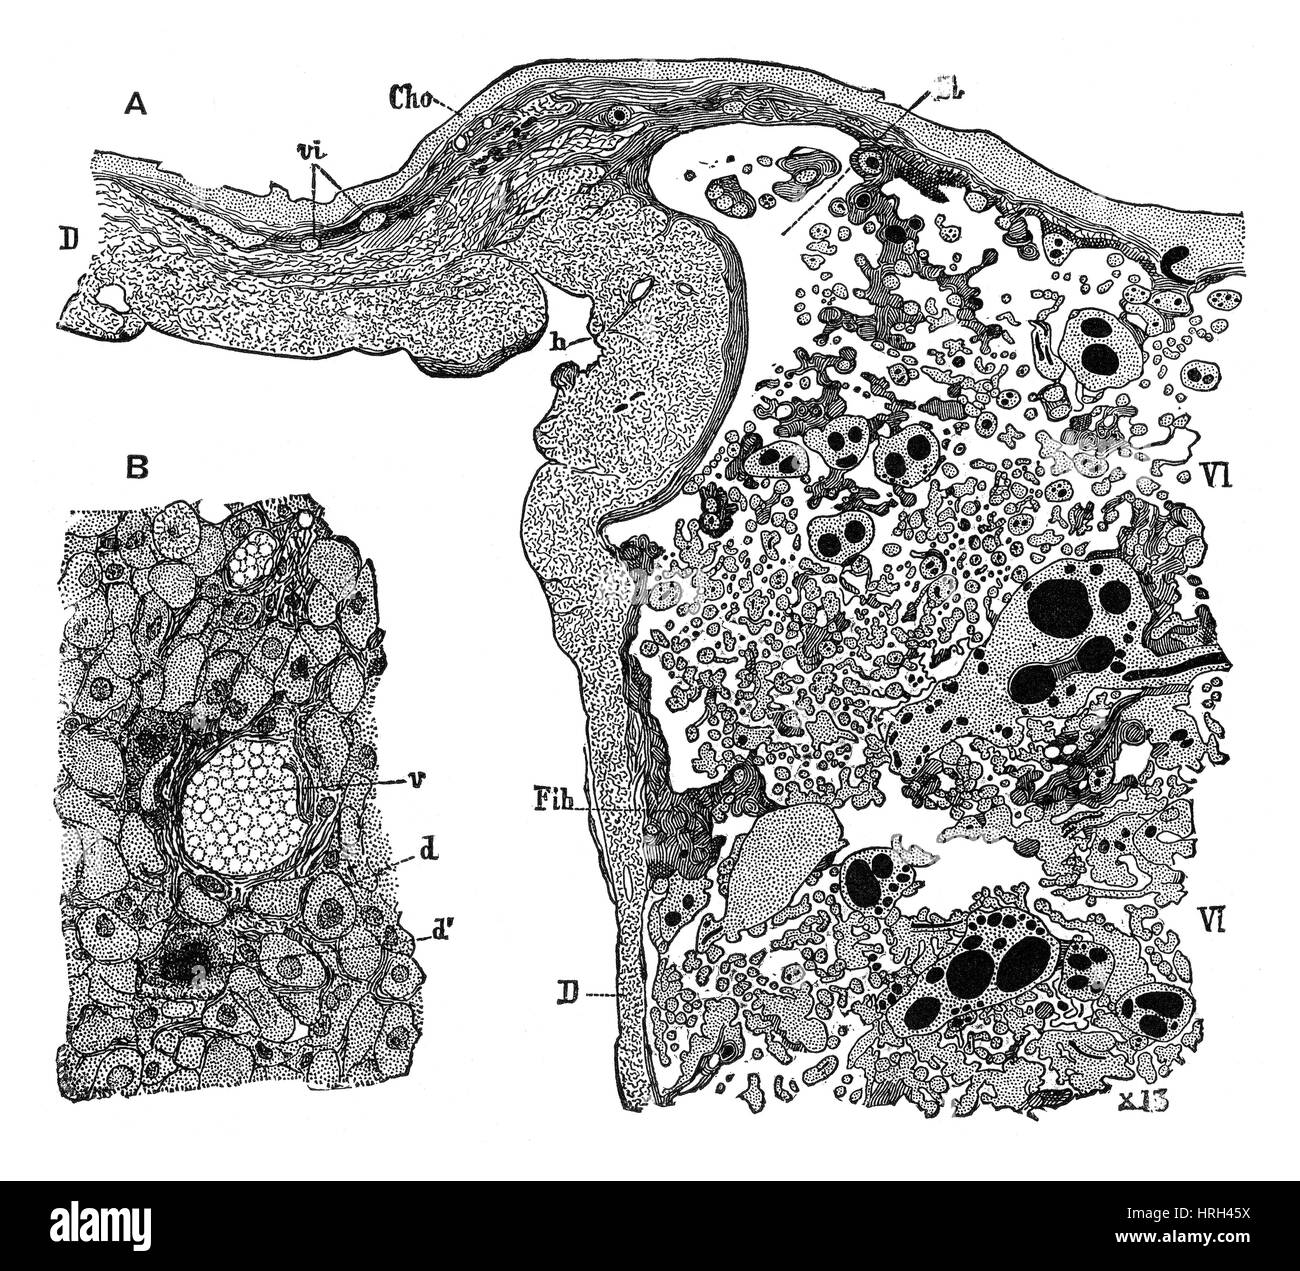

Structure du placenta Banque D'Imageshttps://www.alamyimages.fr/image-license-details/?v=1https://www.alamyimages.fr/photo-image-structure-du-placenta-134986150.html

Structure du placenta Banque D'Imageshttps://www.alamyimages.fr/image-license-details/?v=1https://www.alamyimages.fr/photo-image-structure-du-placenta-134986150.htmlRMHRH45X–Structure du placenta